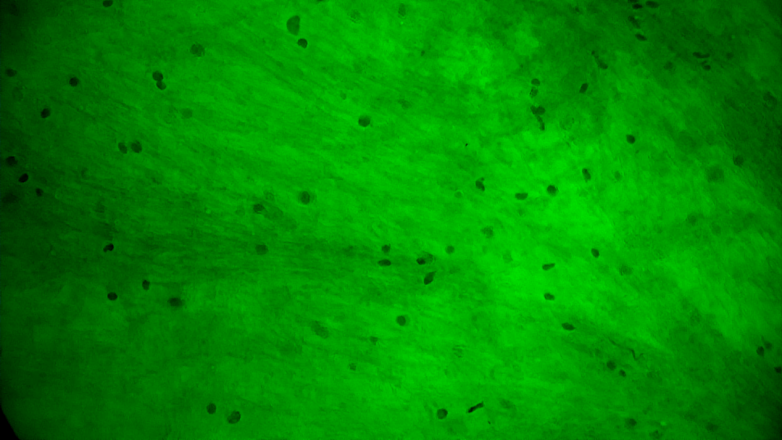

术中EndoSCell®细胞图像如下:

2.手术切缘处发现的正常脑白质:细胞核形态正常,密度低且分布均匀。